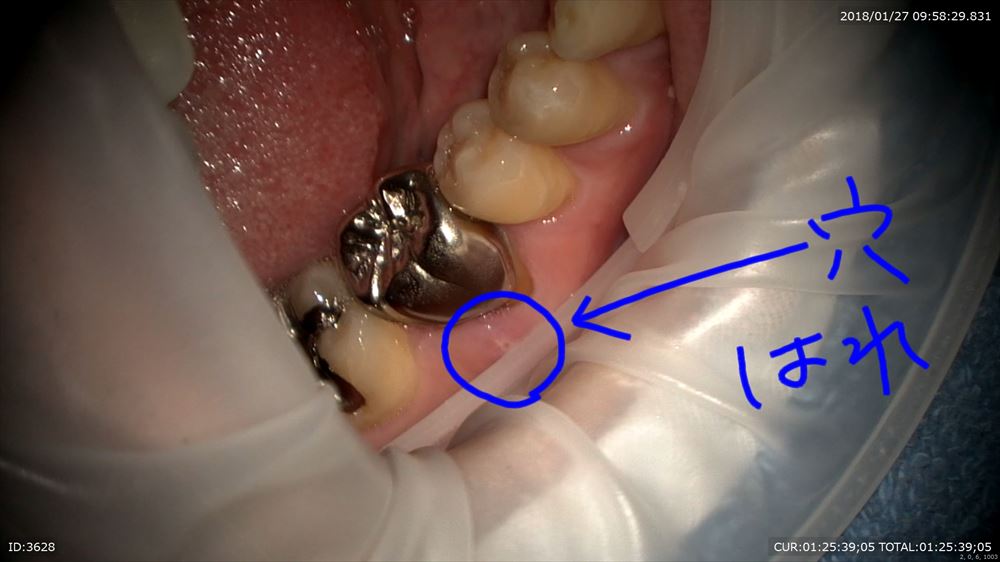

1つ目これがサイナストラクト

見えにくいですが穴が開いています。膿が出てきた!!CTでは約8mmの膿が確認。歯科ドック大切。

被せ物を外して、ラバーダム。これがないと失敗します。